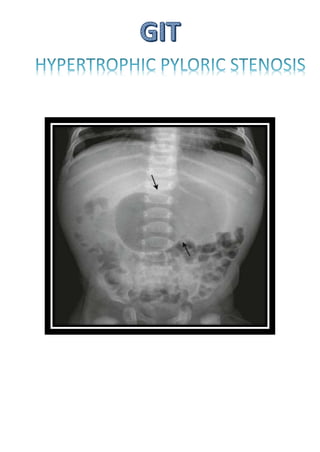

Double bubble sign

Triple bubble sign